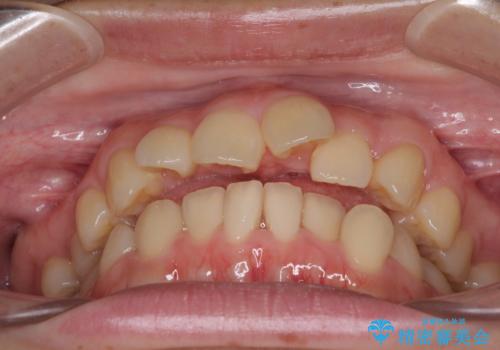

- デコボコと飛び出した前歯を治したいとのことで来院された患者様です。

ゴムかけを活用して上顎歯列全体を後方移動し、IPR(歯と歯の間を削る)によってデコボコが解消するように設計し、インビザラインにより治療を行うこととしました。

後方移動に際し、上下顎の親知らずは4本とも抜歯することとしました。

毎日しっかりと装着してくださったので、概ねシミュレーション通りに歯を移動させることができました。

治療前には接触することのなかった上下の前歯が接触するようになり、食事の際前歯でものをかみ切れるようになりました。